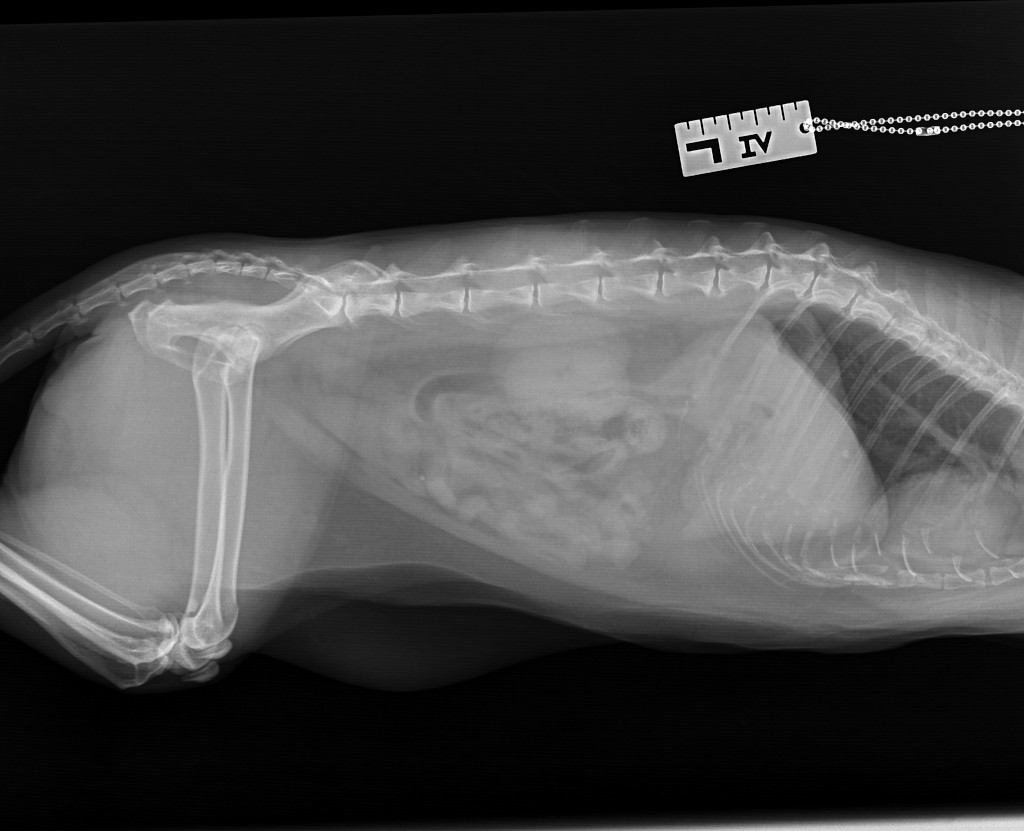

Nachdem wir wussten, wo wir hinfahren müssen, haben wir Balu eingepackt. Dort angekommen hat die Tierärztin ihn nach Strich und Faden untersucht, konnte aber akut mit den ihr zur Verfügung stehenden Hilfsmitteln nichts feststellen, was die Probleme verursacht. Zu diesem Zeitpunkt konnte er sich schon gar nicht mehr bewegen. Also nächste Station Tierklinik. In unserem Fall AniCura Frankfurt. Das waren die einzigen in der Umgebung, die ans Telefon gingen. Es erfolgte eine erneute allgemeine Untersuchung sowie ein Röntgenbild, aber es konnte wieder keine Ursache auf die Schnelle gefunden werden. Wir ließen ihn für weitere Untersuchungen vor Ort und waren irgendwann kurz nach Mitternacht wieder Zuhause – mit den Nerven am Ende und ohne Balu.

Doch erstmal zurück zum MRT: Damit gab es endlich eine neue Erkenntnis. Auf der Höhe des 2. Halswirbels ist auf den Bildern klar eine starke Verengung zu erkennen. Da war sie endlich, die Ursache für seine Probleme. Zwei Möglichkeiten kamen nun in Frage: Ein Tumor oder ein Rückenmarksinfarkt. Ohne eine Biopsie lässt sich das nicht feststellen, was jedoch eine erneute Narkose und eine kleine Operation bedeuten würde. Außerdem sprachen ein paar Punkte wie z.B. das plötzliche Auftreten eher für einen Infarkt. Entsprechend kam von der Klinik der Vorschlag ihn nach Hause zu holen und 1-2 Wochen zu beobachten. Abholen wollten wir ihn mittlerweile sowieso. Wir rechneten schließlich fest damit, dass der nächste Schritt die Einschläferung ist und das hätten wir bei seinem Zustand lieber zu Hause gemacht.

Der weiße Klotz durch den die grüne Linie geht – das ist es!